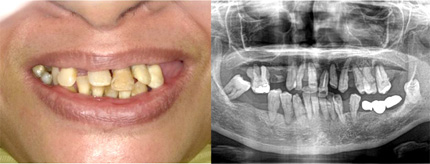

オールオン4の治療例:1

治療前

治療後

オールオン4の治療例:2